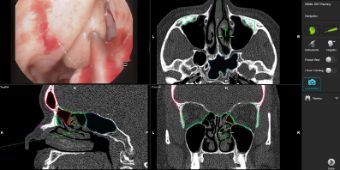

Das Ausschöpfen konservativer Therapiemöglichkeiten steht bei chronischen Entzündungen der Nase und Nasennebenhöhlen zunächst im Vordergrund. Sollte eine Operation erforderlich werden, bieten wir unseren Patienten minimal-invasive endoskopische OP-Techniken an. Dabei können wir in den weit überwiegenden Fällen auf eine Tamponade der Nase verzichten. Bei Bedarf stehen uns moderne computergestützte Navigationsverfahren zur Verfügung. Dadurch wird ein operatives Vorgehen mit maximaler Präzision unterstützt und unseren Patienten die größtmögliche Sicherheit im Rahmen des Eingriffs geboten.

Neben den in der Regel endoskopisch durchgeführten Operationen kommt es in Einzelfällen, insbesondere bei Tumorerkrankungen der Nebenhöhlen oder der Nasenhaupthöhle auch zu der Notwendigkeit, einen äußeren Zugang zu wählen. Auch hier wird der Zugang dem Bedarf der Erkrankung und Ausdehnung des Befundes angepasst und kosmetisch möglichst zufriedenstellend gewährleistet. Gerade bei Tumorerkrankungen ist der Einsatz der Navigation und eine sehr sorgfältige präoperative Planung zur größtmöglichen Schonung wichtiger benachbarter Strukturen wie der Schädelbasis und des Auges von besonderer Bedeutung.